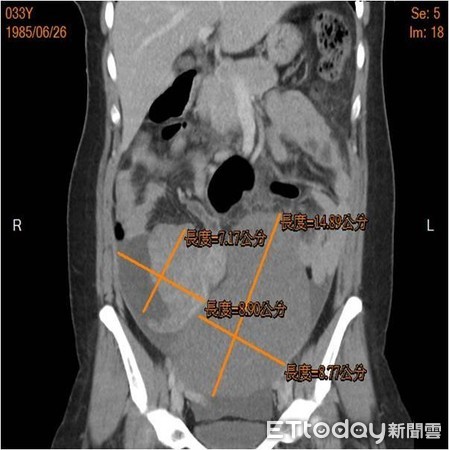

▲患者的子宮上有大大小小的腫瘤,最大約14x8公分。(圖/小港醫院提供)

高雄一名33歲林小姐,因突發性腹痛就醫,懷疑自己得了腸胃炎,然而服用藥物後,情況並未顯著改善,還出現發燒情況,直到醫師透過電腦斷層檢查後,才發現子宮上有大大小小的腫瘤,最大約14x8公分,且合併有腹水,最後以手術切除了10顆肌瘤,過程中最大顆帶蒂的肌瘤,還有扭轉、缺血壞死的情形,術後林小姐已順利回到工作崗位。